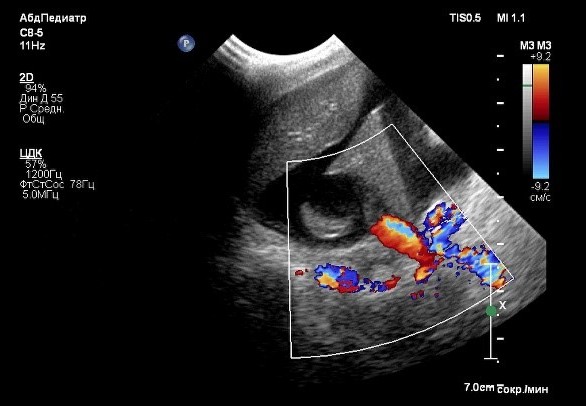

В этот период состояние пациента ухудшилось (фото 3), прогрессировал более выраженный асцит. Это привело к затруднению двигательной активности собаки, и владельцы приняли решение о повторном проведении ультразвукового исследования брюшной полости.

В ходе проведения УЗИ выявлена отрицательная динамика в отношении количества свободной жидкости в брюшной полости (до 6 см на просвет). Также обнаружены увеличение отека паренхимы поджелудочной железы, характеризующееся появлением признаков, известных как «тигровая поджелудочная железа», и нефролитиаз (фото 4). Данные изменения свидетельствуют о развитии тяжелой портальной гипертензии, что требует проведения незамедлительной диагностики для установления причин и разработки плана лечения.